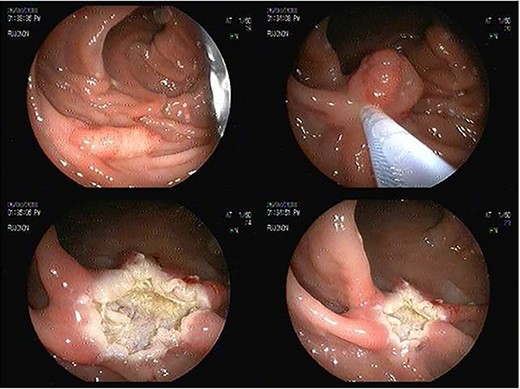

We report the case of a 55-year-old woman diagnosed with of a 3 cm × 4-cm polyp in the ascending colon, who was admitted for an endoscopic resection. At the beginning of the procedure the submucosa was infiltrated with adrenaline, methylene blue and saline solution, and then a heated wire loop resection was made (Fig. 1). Six hours after the procedure, the patient complained of nausea, multiple emetic episodes and abdominal pain in the right iliac fossa 10/10 intensity on an analogue scale of pain. She was transferred to the emergency department, her vital signs were normal and no physical examination signs of peritoneal irritation were found.

Endoscopic sessile polyp resection sequence with use of heated wire loop.